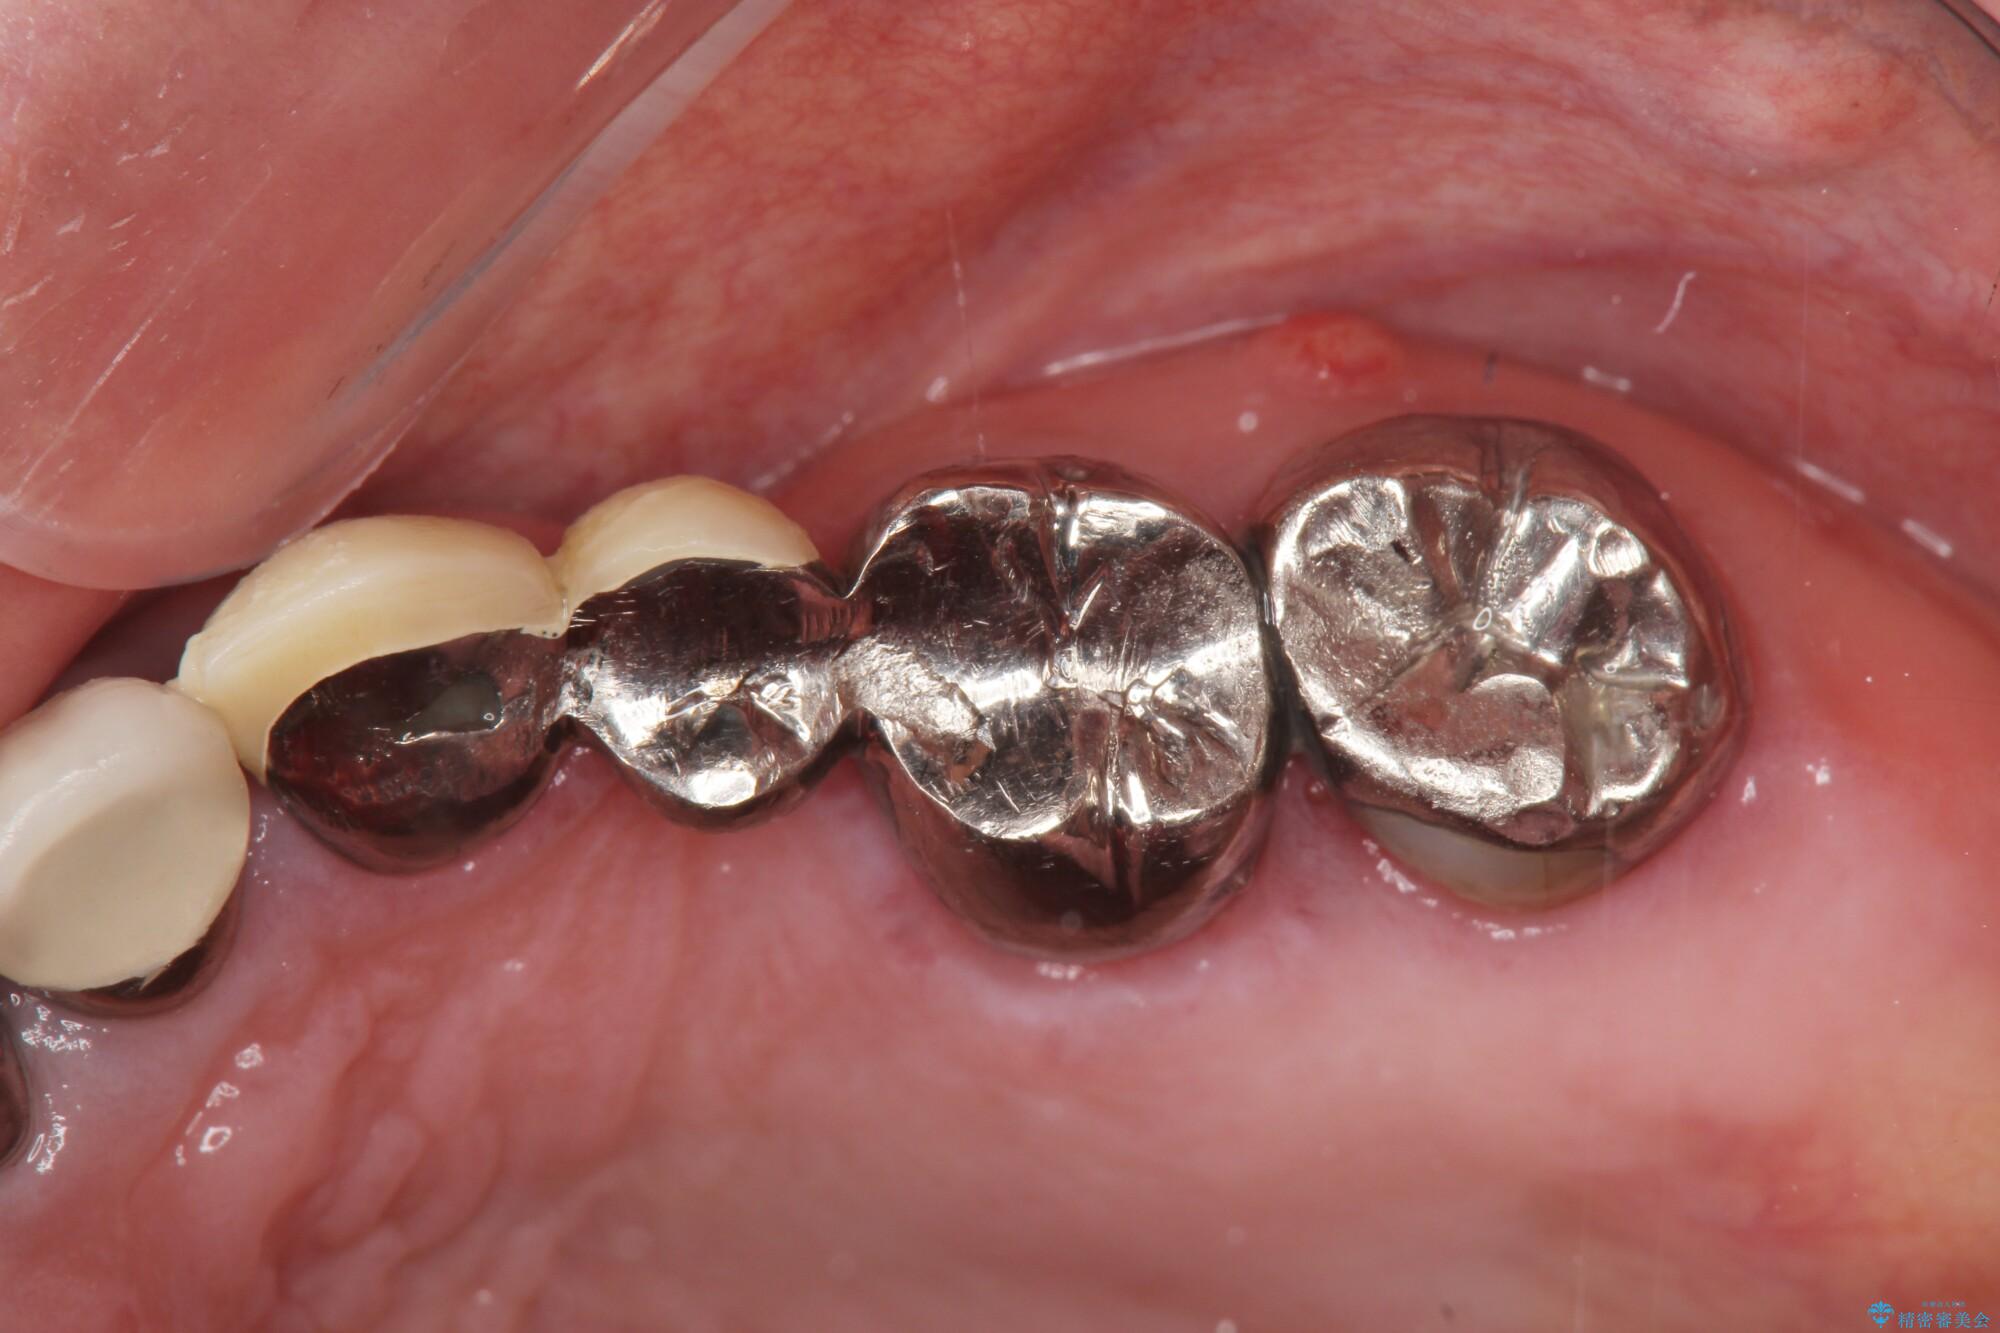

銀歯をジルコニアセラミックへと換えることで、審美性・清掃性の高い仕上がりを目指します。

ブリッジに審美的でないイメージやあまり良くないイメージをお持ちの方を多々お見受けしますが、適切な設計とすることで、見た目に自然で審美的なブリッジ治療を行うことができます。